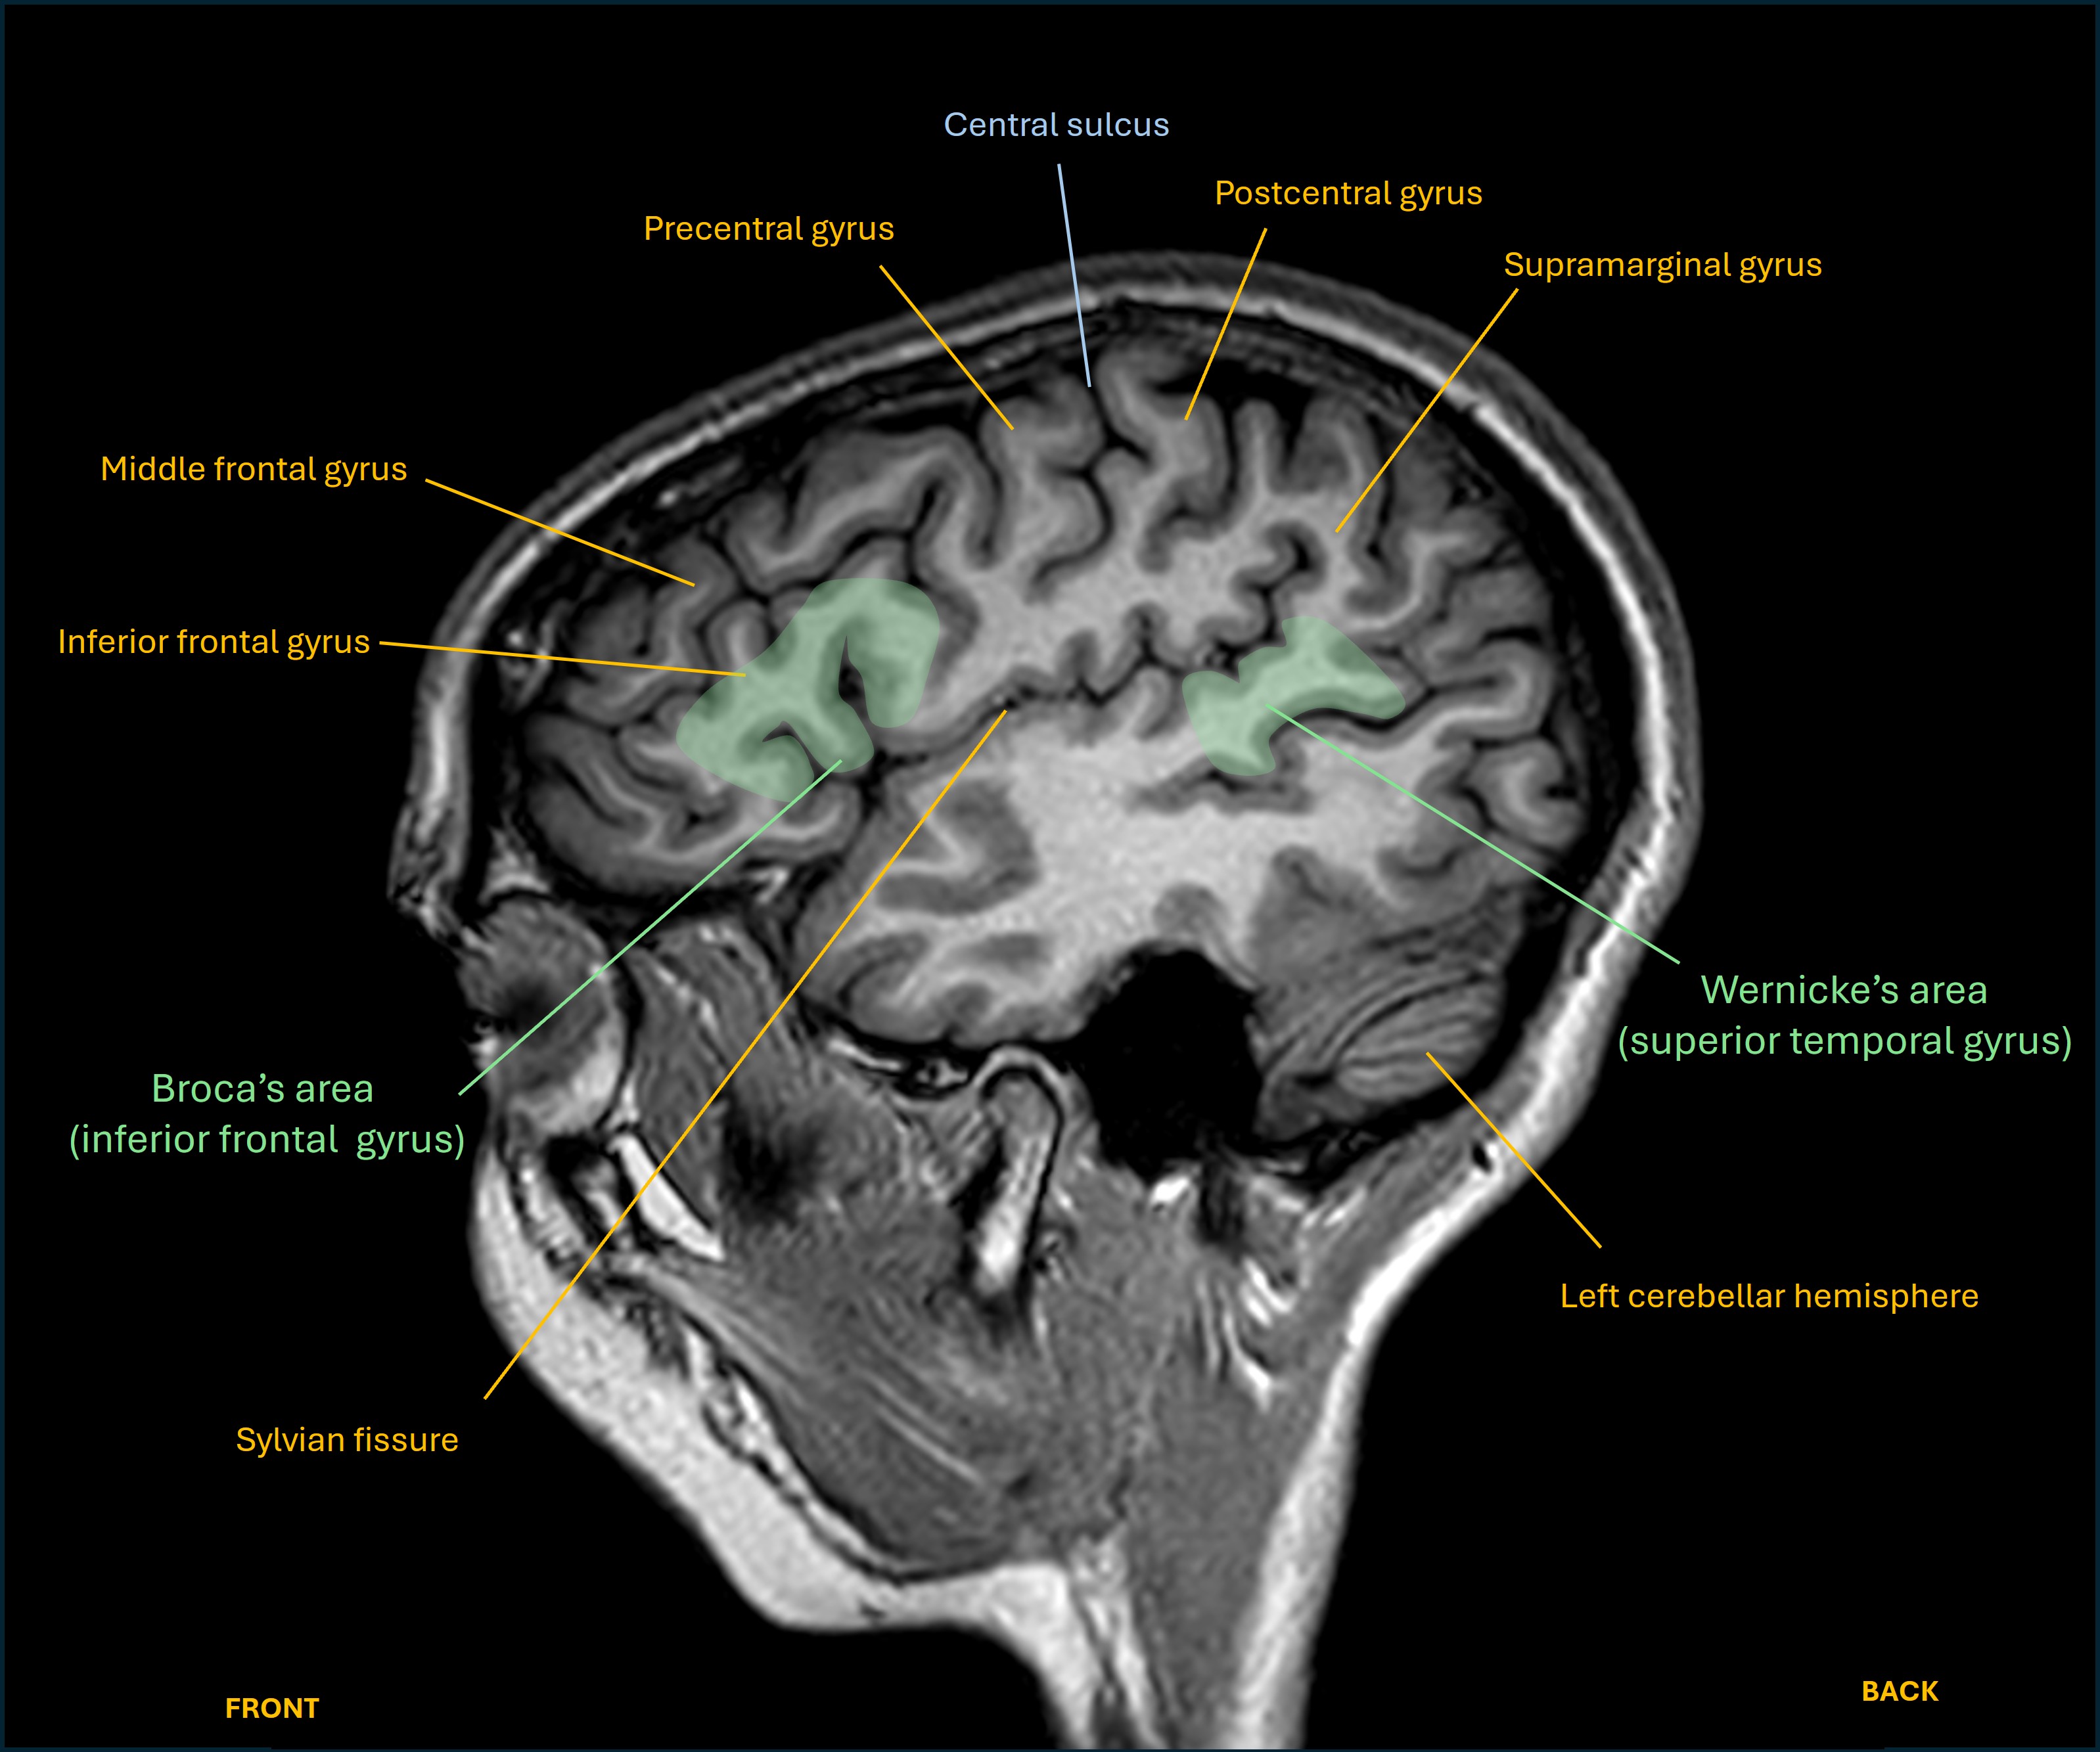

This mixed pattern suggests a lesion somewhere overlapping the left frontal lobe (expressive) and temporal lobe (receptive) language centres, which must involve the subcortical white matter structures connecting these. The fact that the severity is only moderate also fits this - often a lesion centred in the language centre itself produces more profound dysphasia. (Of note, the term aphasia is often used interchangeably with dysphasia - but should really mean a more profound language deficit, or even complete loss of language functions.)

Her dysphasia pattern is different from the two well-known ‘pure’ expressive and receptive forms:

Axial language

Sagittal language